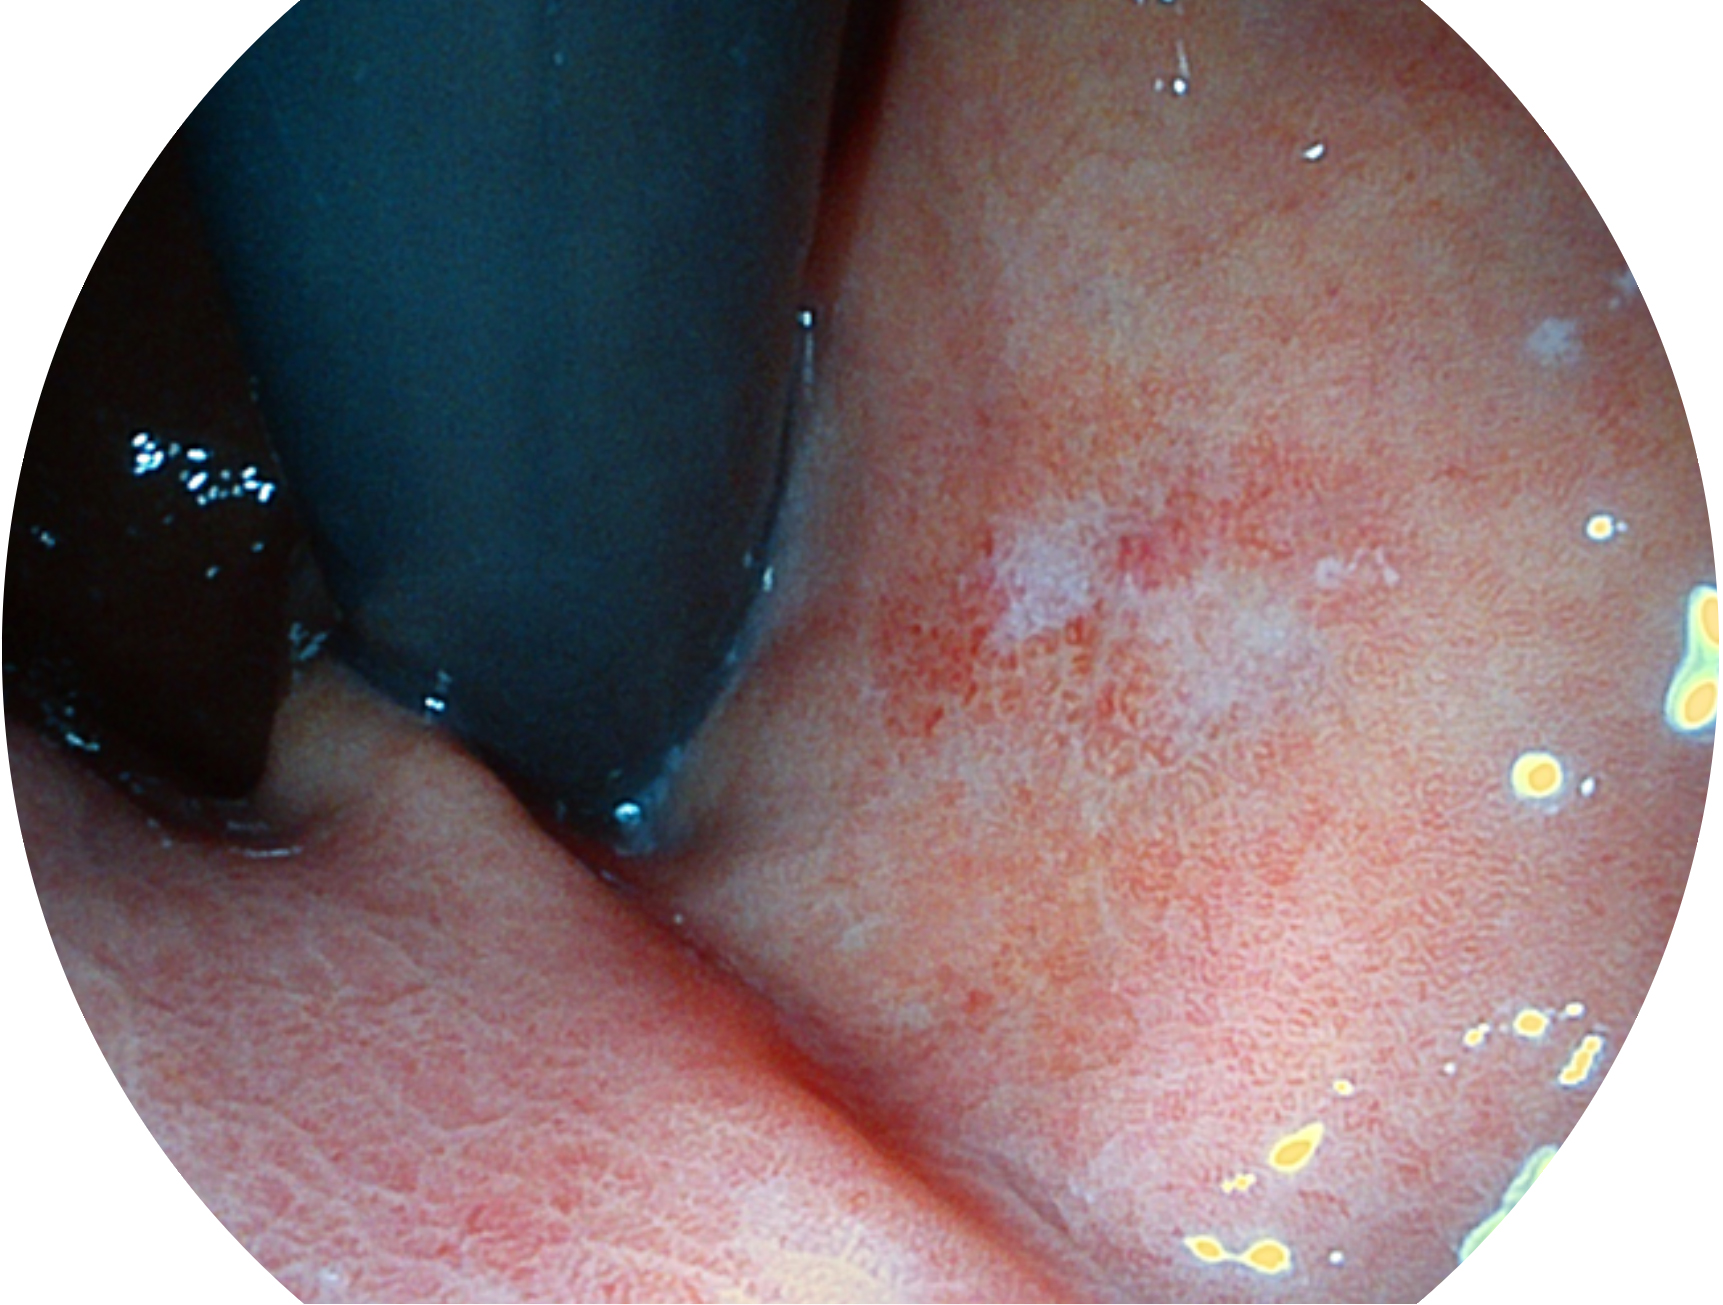

银河集团官网新开发的内镜染色技术,主要是基于多波长LED 光源的开发,VLS-55Q 四波长LED 光源是由四个不同颜色的LED光按照相应照明模式所规定的特定发光比例进行合束后形成,合束后形成的照明光的光谱由红光、绿光、蓝光及蓝紫光这四个不同的波段范围构成。具有更高光谱自由度,通过光谱比例的控制,实现了聚谱成像技术,英文全称为“Spectral Focused Imaging, SFI”,缩写为“SFI”和光电复合染色成像技术,英文全称为“Versatile Intelligent Staining Technology, VIST”,缩写为“VIST”。